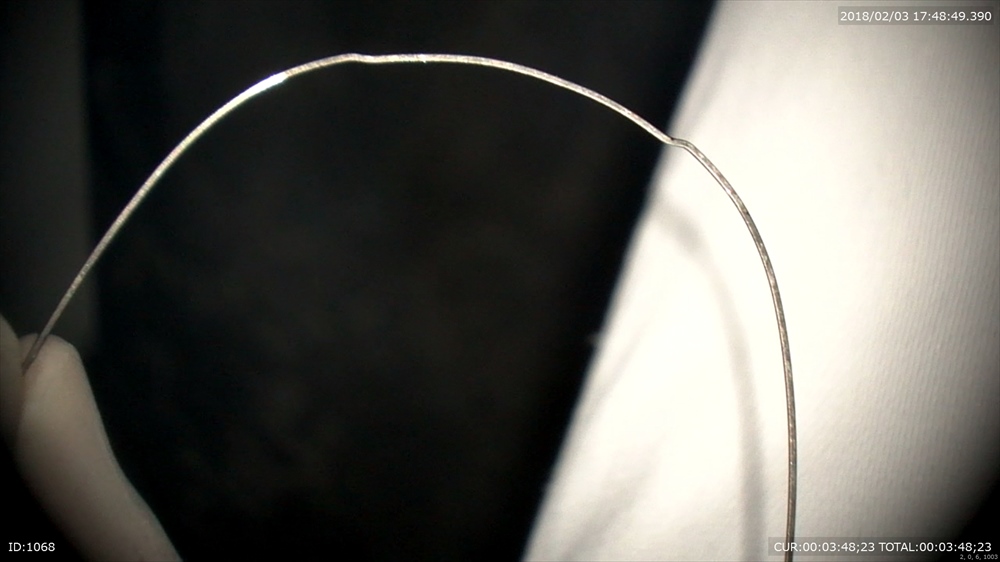

②マイクロスコープをこの様に↓

ここをズーム

25倍

この制度で研磨するので歯茎さわりません。

だから痛みがないし血はでません。

この精度 血がでないでしょ。だから術後も楽~